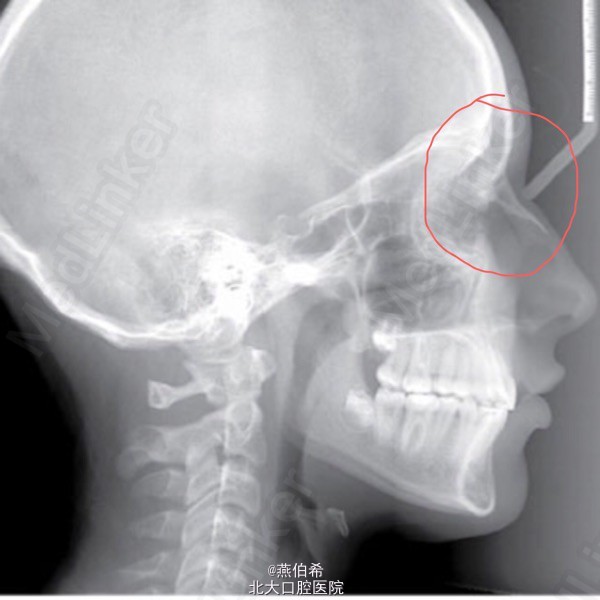

从侧位片看人种的面部差异

还记得头侧片上N(Nasion)点的定义吗?"鼻额缝的最前点"。你在量片子的时候能找到中国人的N点不?我怀疑绝大多数都是矇的。我们蒙古人种眼睛凸,眼眶浅,而高加索人种眼窝深,很好找N点。从当代的审美看,人家从遗传上就好看。